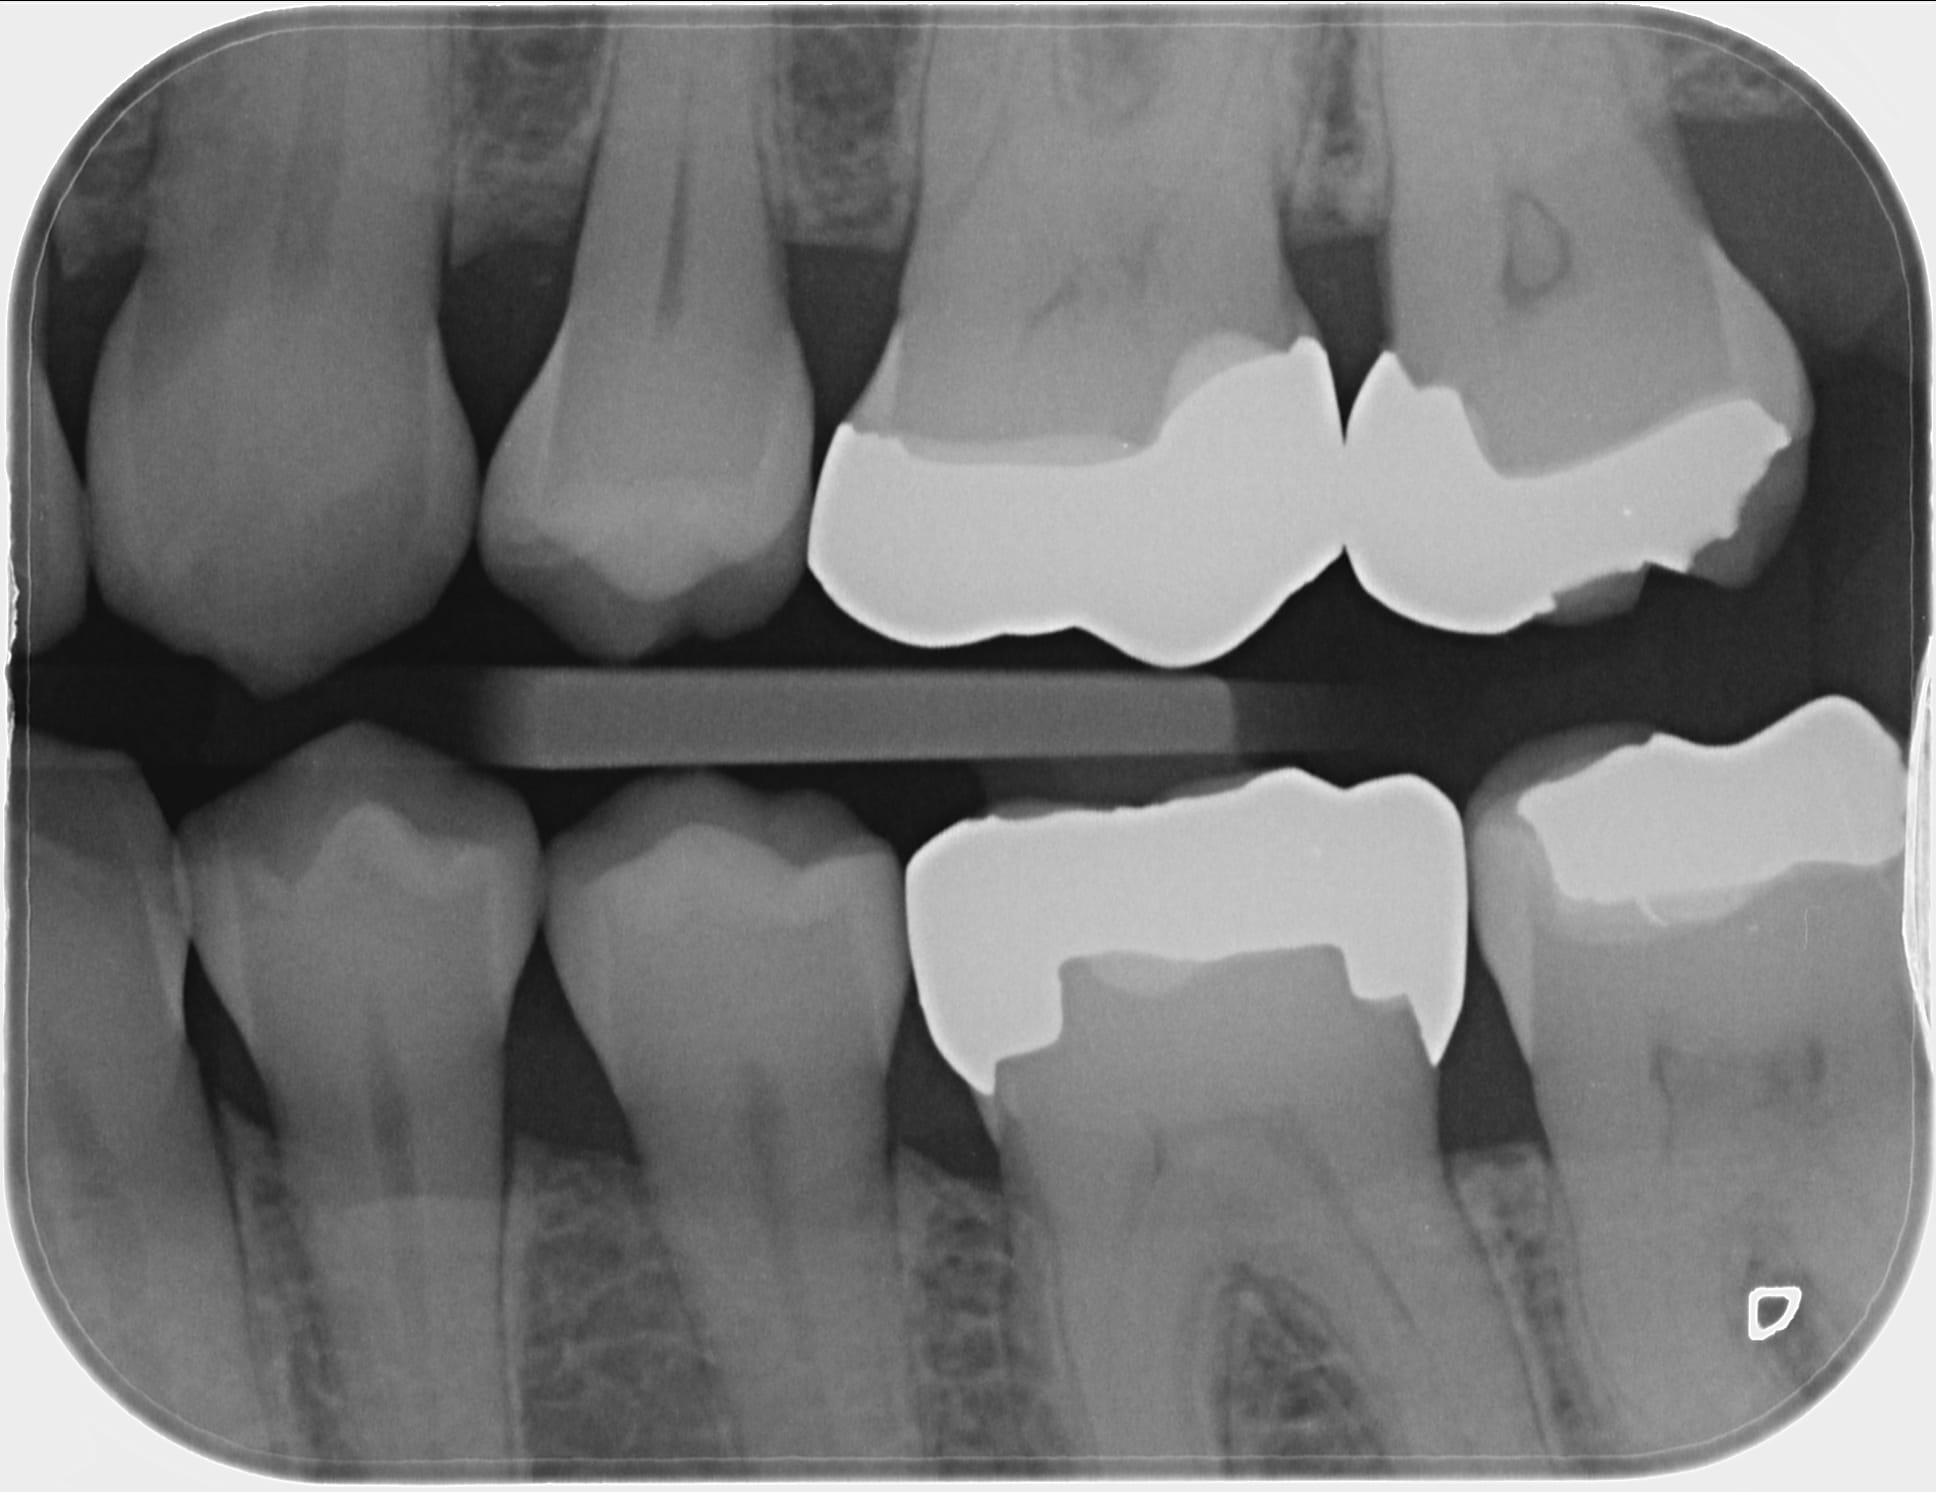

> > Au vu de la préop, ça motive pour garder vivante ;)

> Par contre, c'est vrai que l'endo en seconde intention sera compliqué.

Je me suis fait la même réflexion mais la dent n'a pas l'air plus calcifié maintenant qu'en pré opératoire donc tu n'aurais rien à te reprocher. Beau boulot et merci pour le partage.